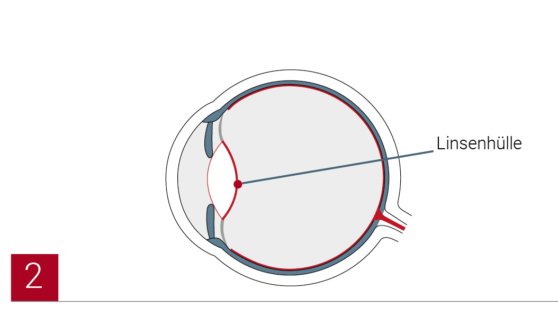

Die vordere Linsenhülle wird kreisrund geöffnet. Dann wird der Linsenkern entfernt. Der Rest der Linsenhülle bleibt erhalten und dient als ‘Halteapparat’ für die neue Linse.

Der Operateur setzt die neue Linse mit einem Injektor in das Auge ein. Die Linse entfaltet sich und wird vom Operateur in der leeren Linsenhülle richtig platziert. Sie kann ein Leben lang im Auge bleiben und kann entweder monofokal oder multifokal sein. Da eine Monofokallinse nur einen Brennpunkt hat, ist der Patient nach der Operation noch auf eine Brille angewiesen. Eine Multifokallinse hingegen hat mehrere Brennpunkte. Sie ermöglicht scharfes Sehen in unterschiedlichen Entfernungen und so ein brillenfreies Leben.

Die vordere Linsenhülle wird kreisrund geöffnet. Dann wird der Linsenkern entfernt. Der Rest der Linsenhülle bleibt erhalten und dient als ‘Halteapparat’ für die neue Linse.

Der Operateur setzt die neue Linse mit einem Injektor in das Auge ein. Die Linse entfaltet sich und wird vom Operateur in der leeren Linsenhülle richtig platziert. Sie kann ein Leben lang im Auge bleiben und kann entweder monofokal oder multifokal sein. Da eine Monofokallinse nur einen Brennpunkt hat, ist der Patient nach der Operation noch auf eine Brille angewiesen. Eine Multifokallinse hingegen hat mehrere Brennpunkte. Sie ermöglicht scharfes Sehen in unterschiedlichen Entfernungen und so ein brillenfreies Leben.